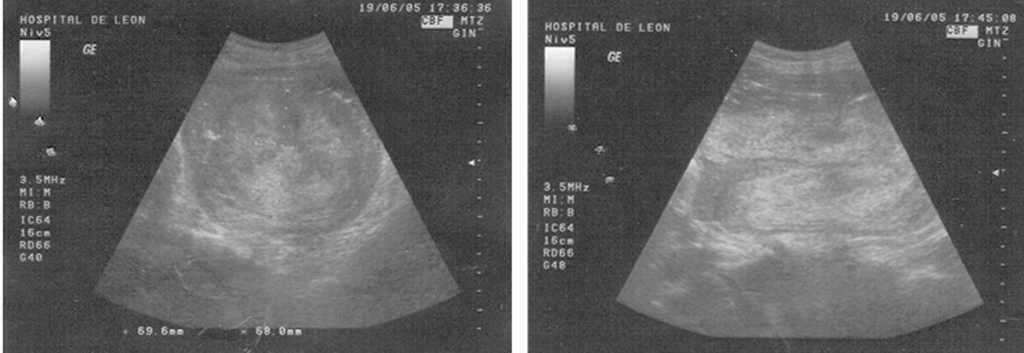

Aunque los síntomas clínicos suelen ser suficientes en la mayoría de los casos para llegar al diagnóstico, se han descrito métodos de imagen que pueden ayudar en el diagnóstico. Hsieh y Lee6 describieron los hallazgos ecográficos de una inversión uterina durante el episodio agudo. En los cortes transversales puede visualizarse «una masa hiperecoica en la vagina con una cavidad central hipoecoica con forma de H» y en los cortes longitudinales se observaba «una depresión longitudinal en forma de U desde el fondo uterino a la parte interior». El uso de la resonancia magnética (RM) también se ha descrito, dando una apariencia al útero similar a la encontrada en la imagen ecográfica; sin embargo, los hallazgos con la RM son mucho más precisos. Estas técnicas pueden colaborar al diagnóstico, sobre todo en aquellos casos en que es menos claro y que la paciente está hemodinámicamente estable para poder someterse a esa evaluación7. En una de la pacientes de nuestra serie, ante las dudas diagnósticas, se realizó a una ecografía en que se visualizó una imagen hiperecoica que ocupaba la luz endometrial, imitando a un mioma submucoso (fig. 1).

Figura 1.Imagen ecográfica de inversión uterina (corte transversal y longitudinal, respectivamente).